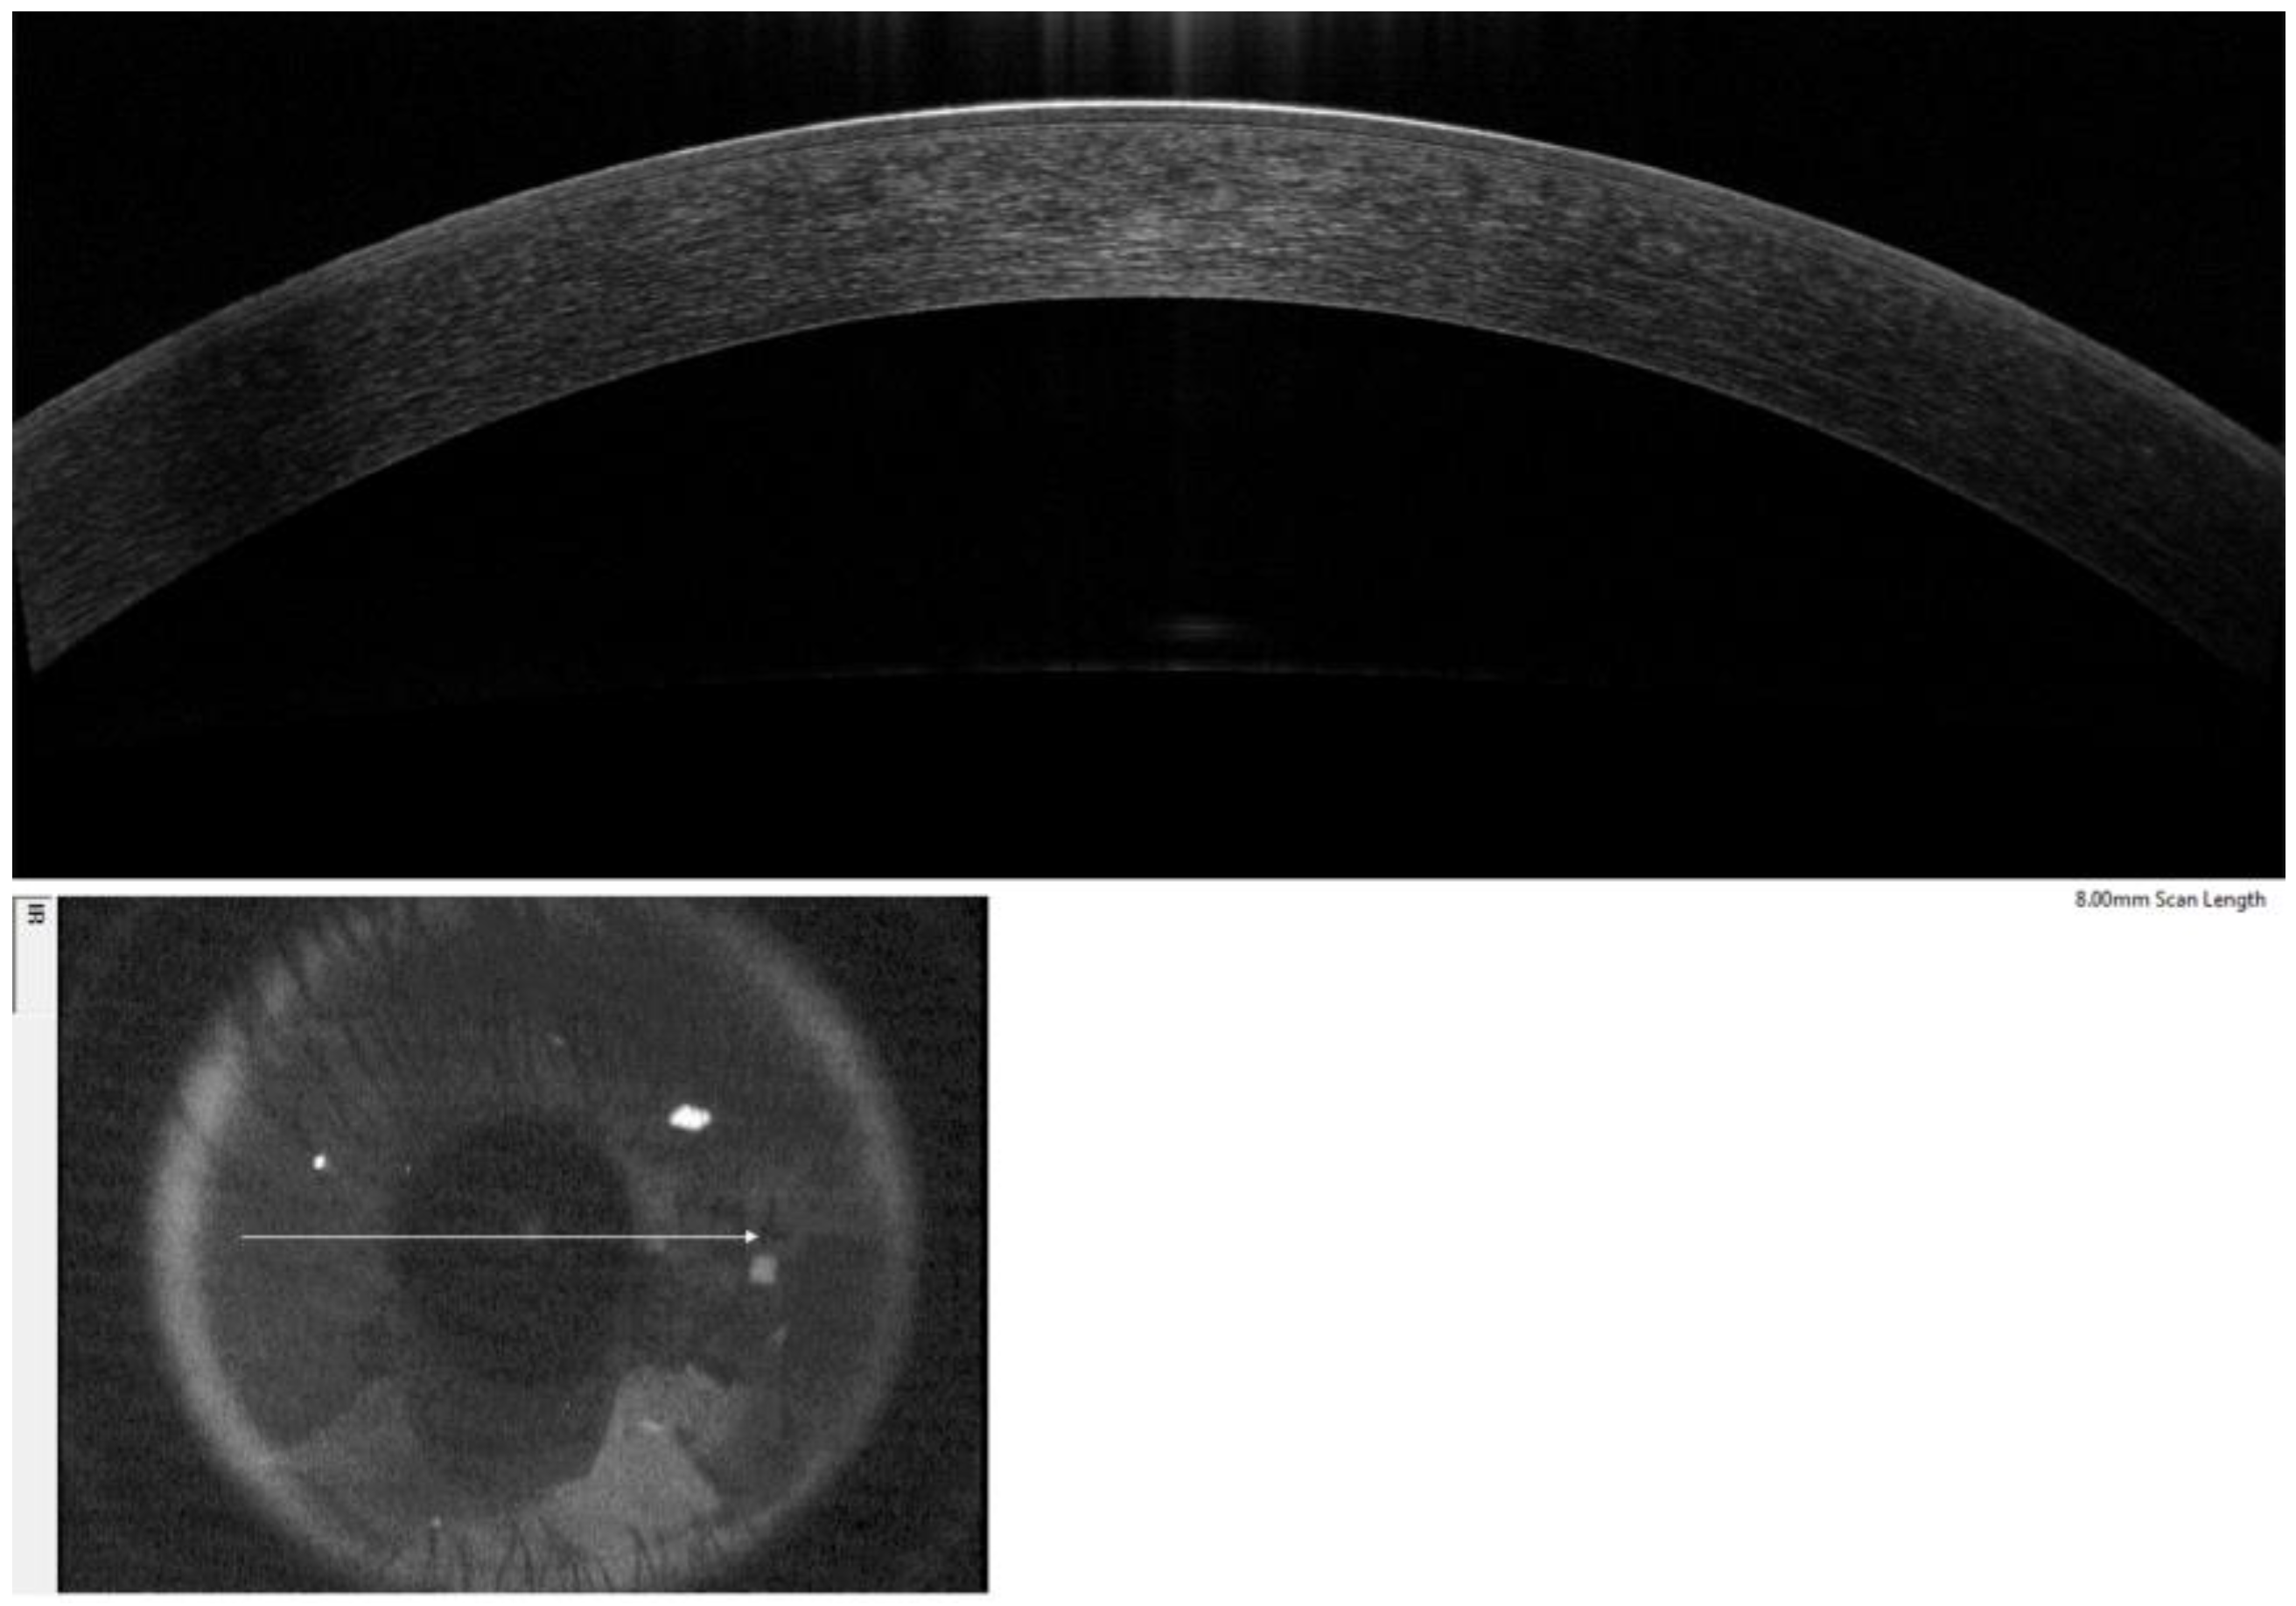

2.2. OCT Imaging and Epithelial Thickness Measurement